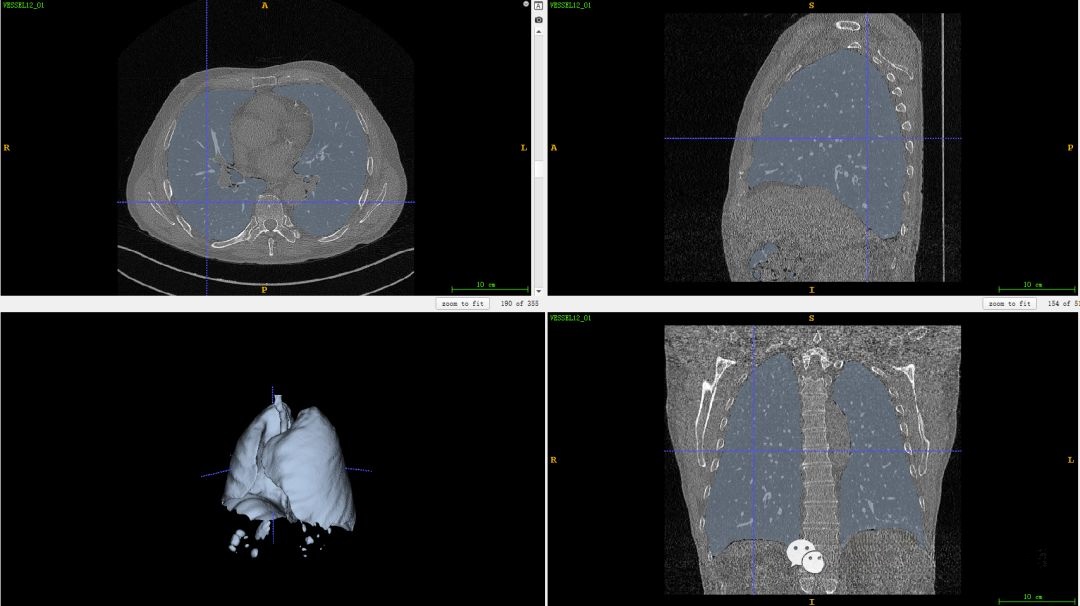

最终将该区域与原始CT图像结合,生成了完整的肺部血管三维模型结果。

在之前的讨论中提到过一种有效的方法是利用Hessian矩阵对血管区域进行增强,在医学图像处理案例(六)——生成血管三维模型中对此进行了详细阐述。其中,我们采用的是一个由多维变量函数的一系列二阶偏导数组成的方阵来进行操作,并通过分析其特征值分布特性来进行管状结构检测。经过这一过程后,在增强后的血管区域图像中可以看出明显的增强效果

通过对比度增强处理后得到的血管区域呈现出明显的明亮特征,在后续处理中我们采用了一种基于阈值的二值化方法对增强后的图像进行分割。具体而言,在完成上述操作后生成的结果中仅保留了具有显著特征的血管区域轮廓。这一过程能够有效地区分出不同类型的血管结构。

最后,我们将该区域与原始图像进行结合,生成肺部血管三维模型结果。